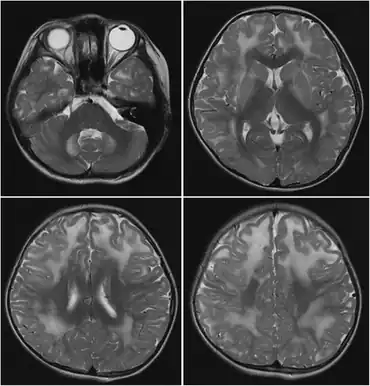

The L-2 form is more common, severe, and mainly affects the central nervous system. The basal ganglia are affected, and cystic cavitations in the white matter of the brain are common, beginning in infancy. This form is chronic, with early symptoms such as hypotonia, tremors, and epilepsy declining into spongiform leukoencephalopathy, muscular choreodystonia, mental retardation, and psychomotor regression.[4]

The D2 form is rare, with symptoms including macrocephaly, cardiomyopathy, mental retardation, hypotonia, and cortical blindness.[7] It is caused by recessive mutations in D2HGDH[8] (type I) or by dominant gain-of-function mutations in IDH2[9] (type II).